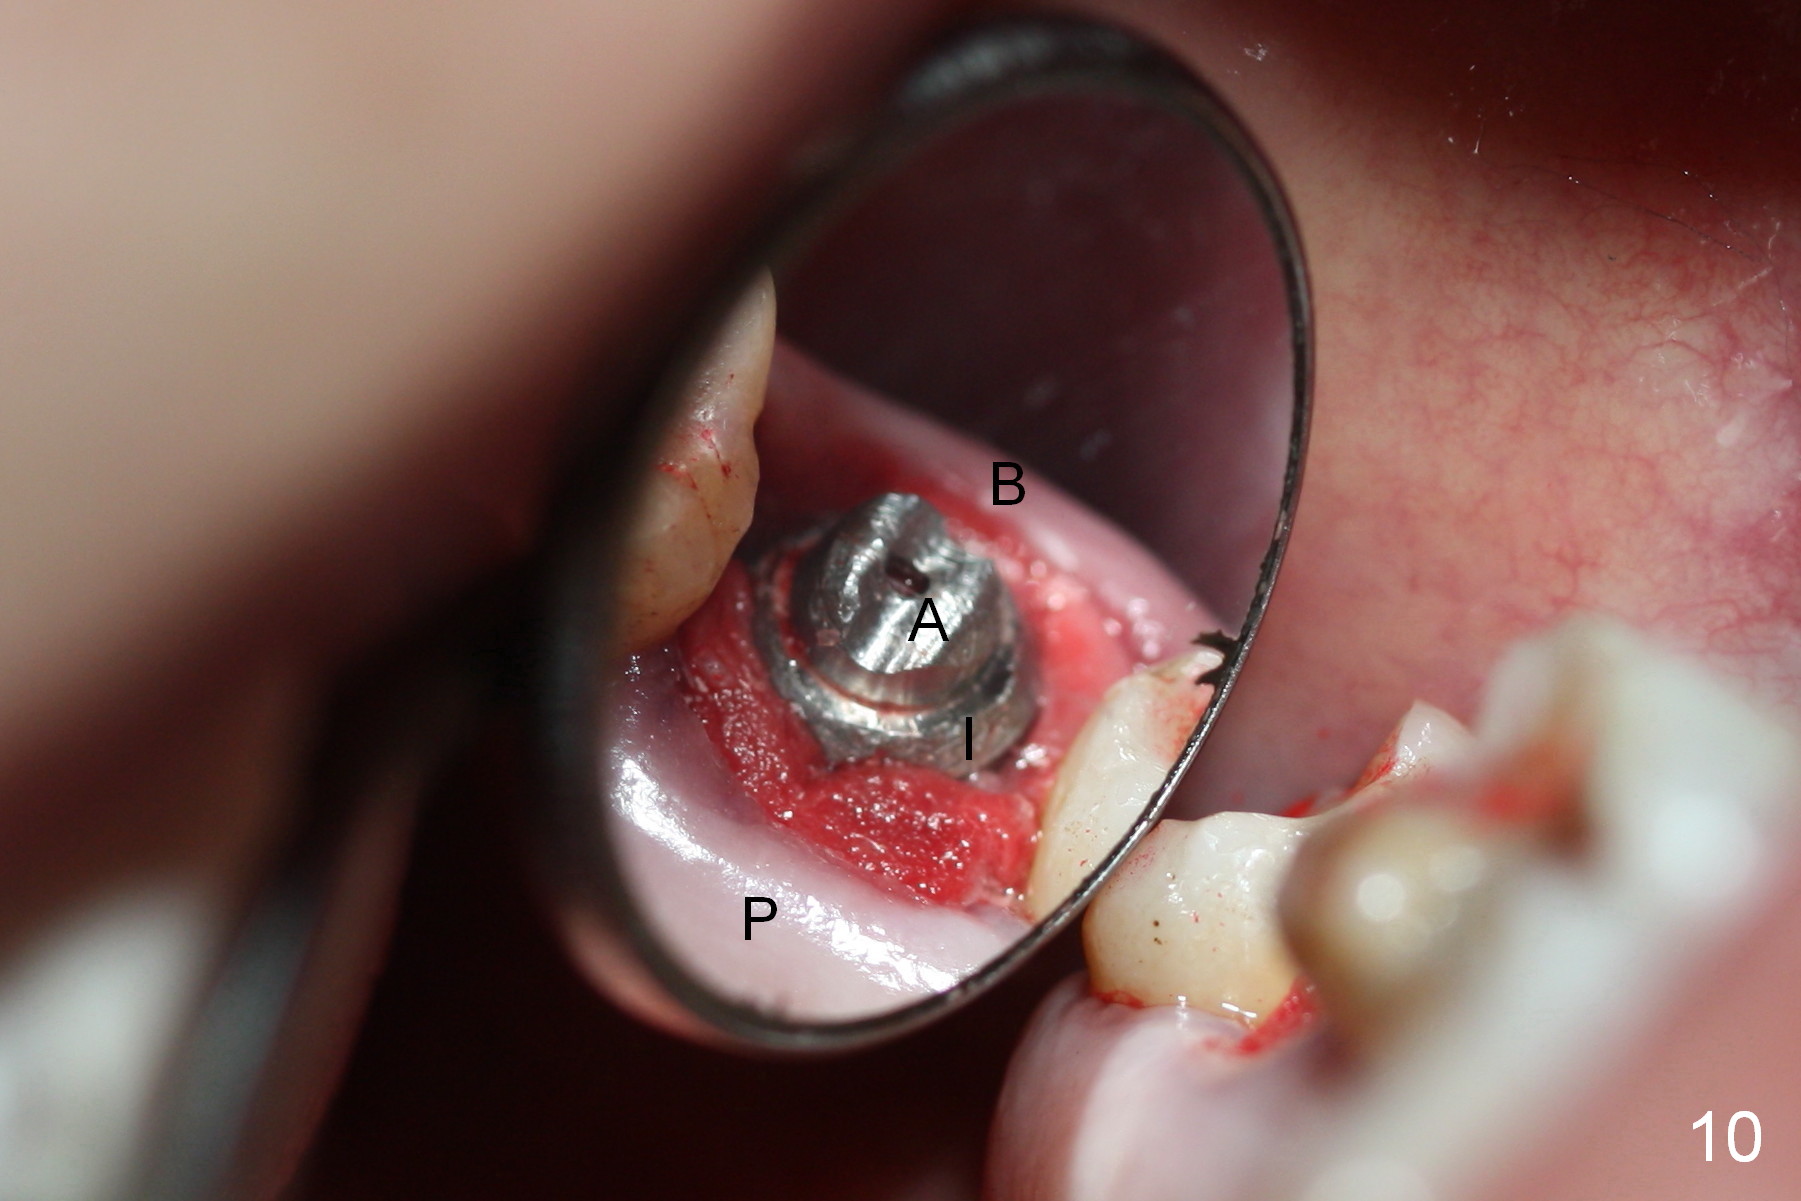

Probably due to bruxism, there is limited vertical restorative space. The margin is subgingival except buccal (Fig.10,11). An immediate provisional (Fig.12 P) appears to have to be fabricated to prevent soft tissue from covering the margin during osteointegration. It is our intention to make gingival envelop larger than the definitive crown cervix. It would be easier to remove a permanent cement later on for peri-implantitis prevention.

The patient returns because of provisional dislodgement 4 days postop. It appears that the socket shrinks (Fig.13 mirror view) with partial resolution of collagen dressing (*, as compared to Fig.10). The provisional is relined and reseated with occlusion checked (Fig.14). There is no sign or symptom of infection. The patient is pleased.